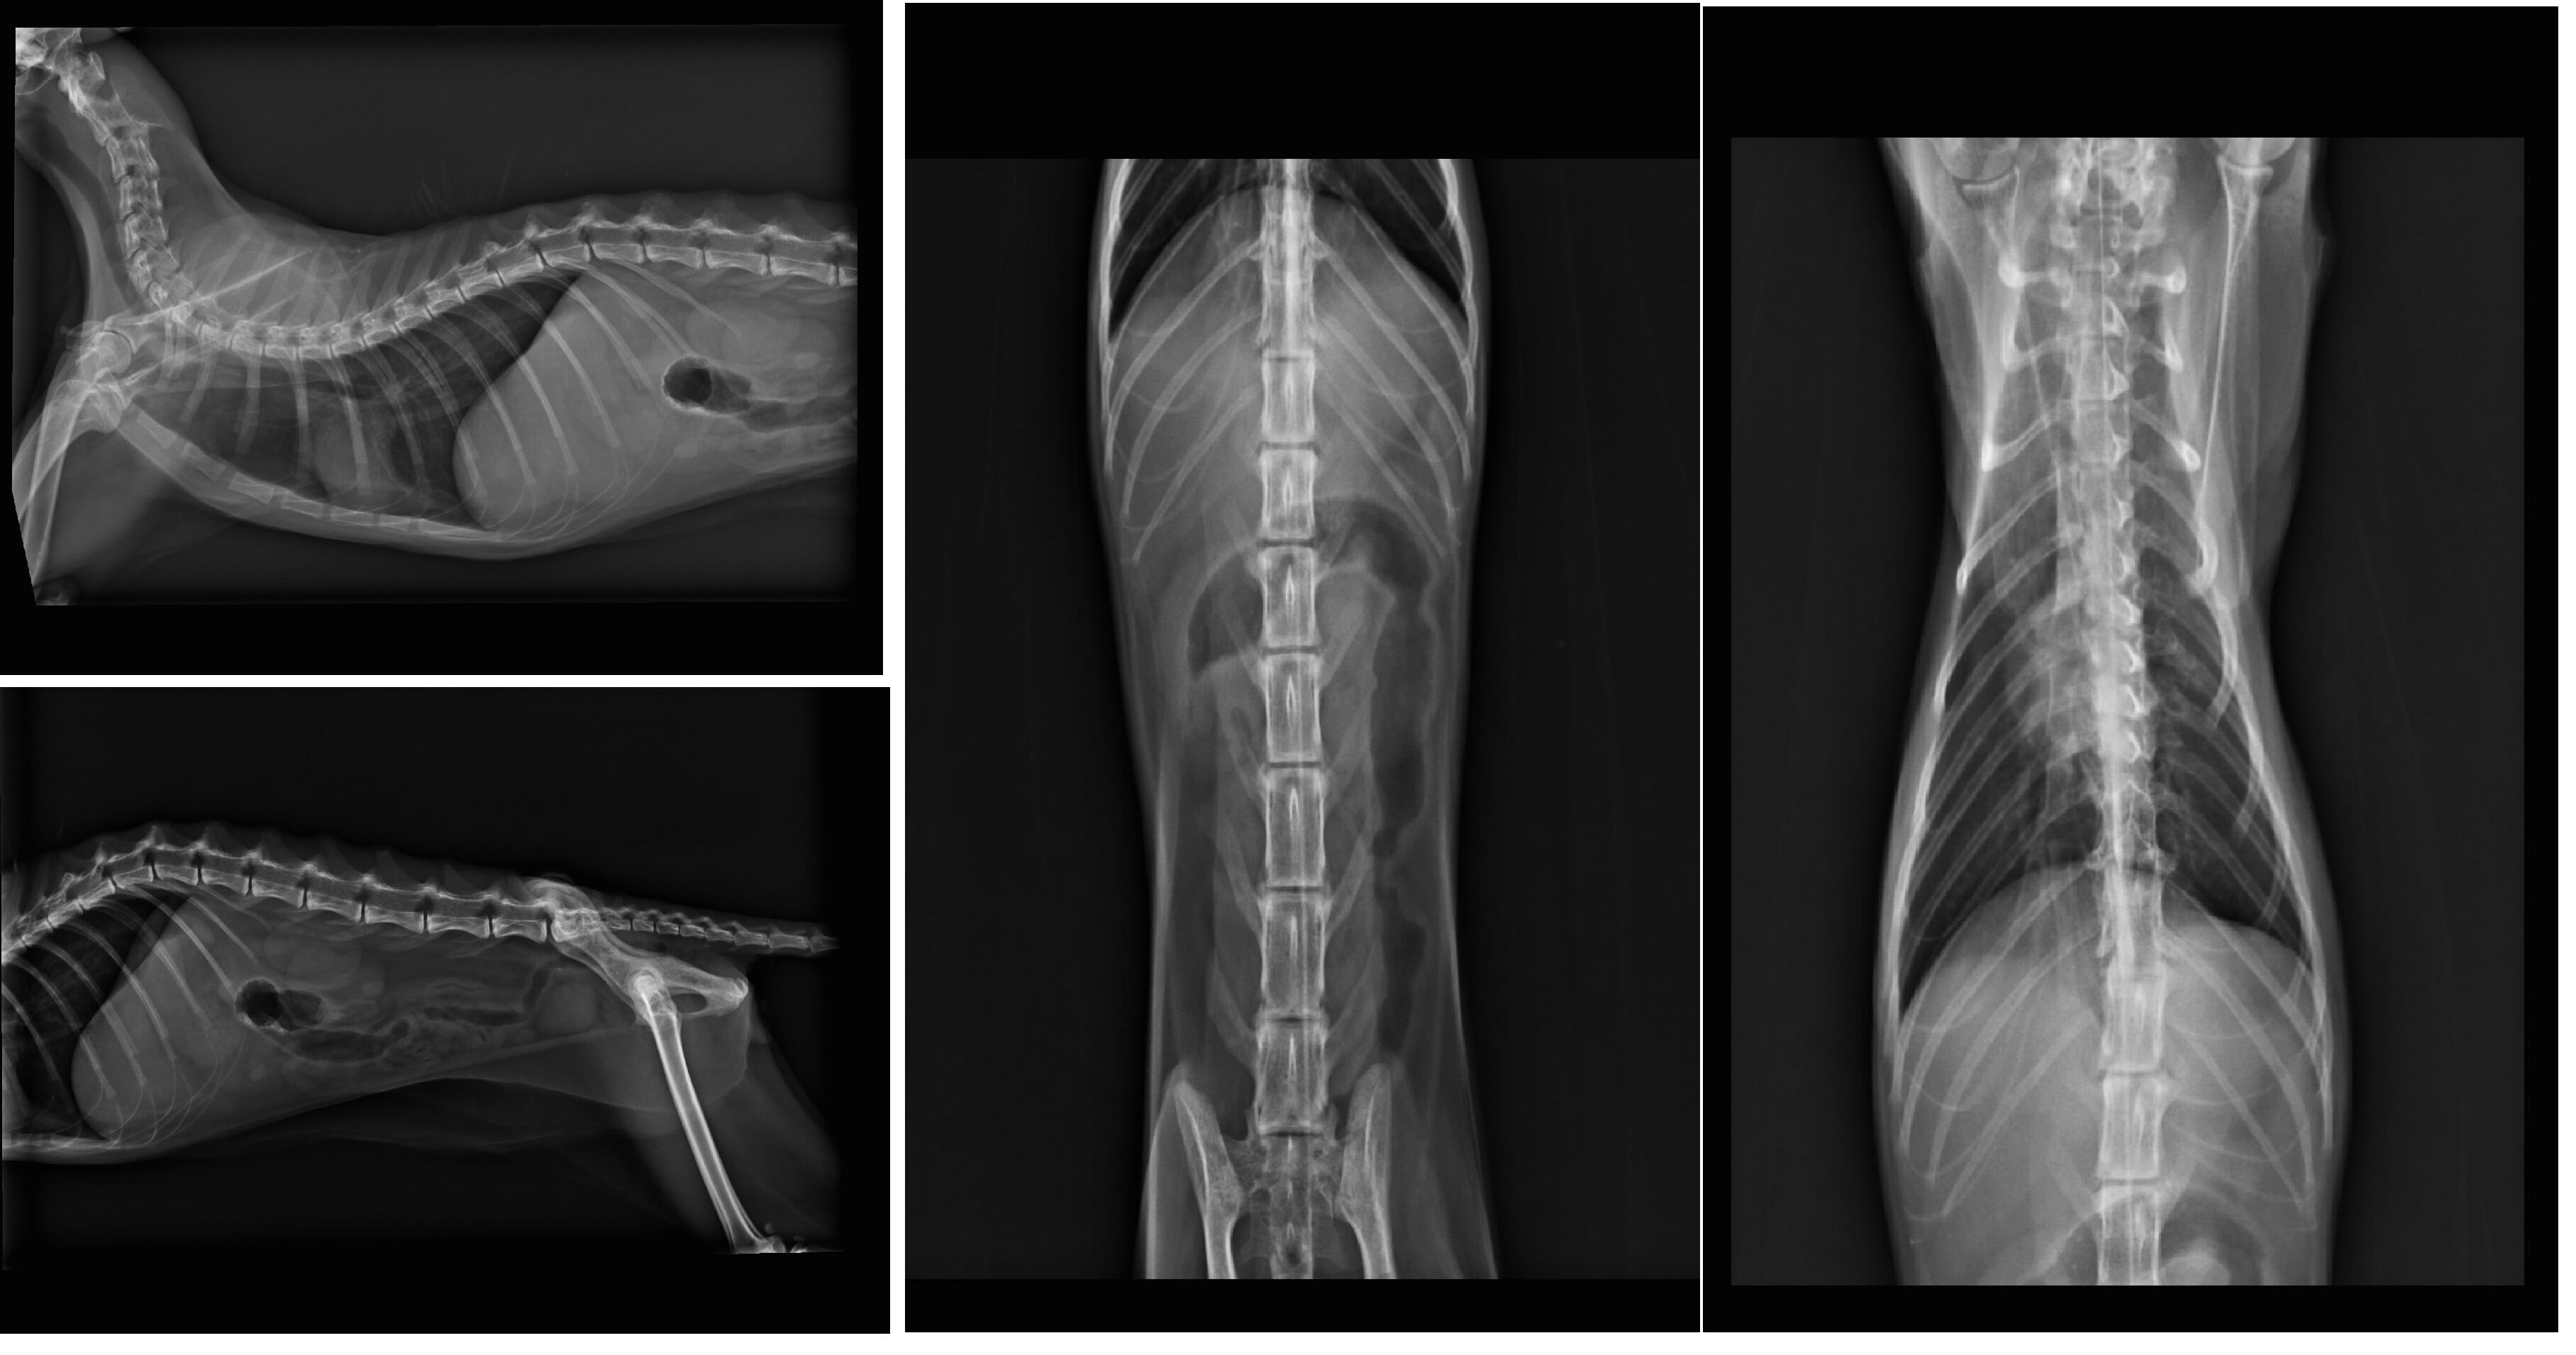

1.血液檢查 2500(9/5)+1200(9/10)+1000(9/13)+300(9/16)

2.X-ray 400*4